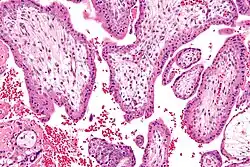

A biópsia das vilosidades coriónicas é um exame de diagnóstico que consiste na recolha de uma amostra das vilosidades coriónicas do útero, as membranas embriónicas exteriores. Embora semelhante à amniocentese, este exame pode ser realizado bastante mais cedo, geralmente entre as oito e doze semanas de gestação, o que em caso de resultados desfavoráveis permite optar pela interrupção da gravidez numa fase precoce. Por ser realizado mais cedo, apresenta um risco de aborto espontâneo significativamente superior ao da amniocentese (1-2%).[1][72]